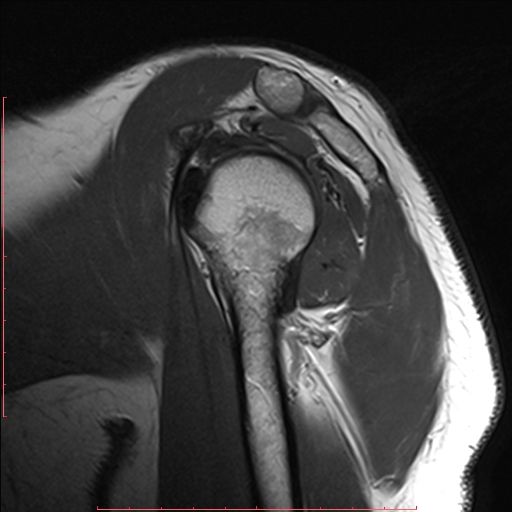

白色文字(排除指定关键词) Imaging Anatomy: interactive PACS-like atlas of radiological anatomy

解剖学模块